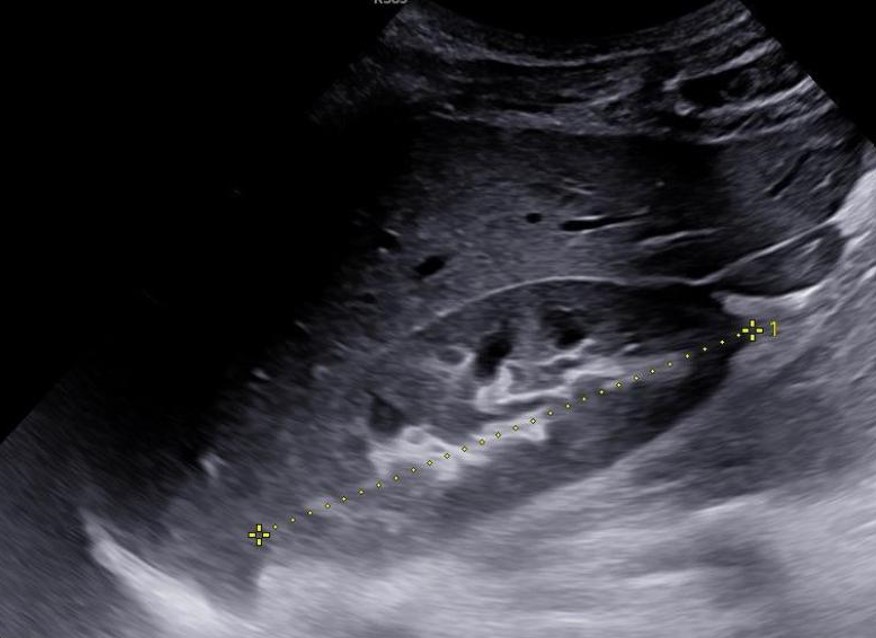

L’échographie ou ultra-sonographie est une technique d’imagerie médicale qui utilise des ondes sonores à haute fréquence pour produire des images des structures internes du corps humain : foie, reins, prostate, vessie, structures digestives, articulations …. Il s’agit d’une technique non invasive et indolore qui permet de visualiser les organes internes, les tissus mous, les vaisseaux sanguins et les structures superficielles du corps. Cette imagerie par ultrasons peut également utiliser l’effet Doppler, échographie-doppler, afin de permettre une analyse précise des structures artérielles ou veineuses et détecter des sténoses, des dilatations ou des obstructions.

- Réalisation de l’examen : Le radiologue ou le manipulateur en radiologie déplace une sonde (transducteur) sur la peau en regard de la zone anatomique à étudier. La sonde émet des ondes sonores à haute fréquence qui pénètrent dans le corps et sont réfléchies par les structures internes. Les échos réfléchis sont capturés par la sonde et convertis en images en temps réel sur un écran. Le médecin radiologue peut demander au patient de « participer à l’examen » en réalisant des apnées ou d’autres manœuvres afin d’améliorer la qualité de l’examen.